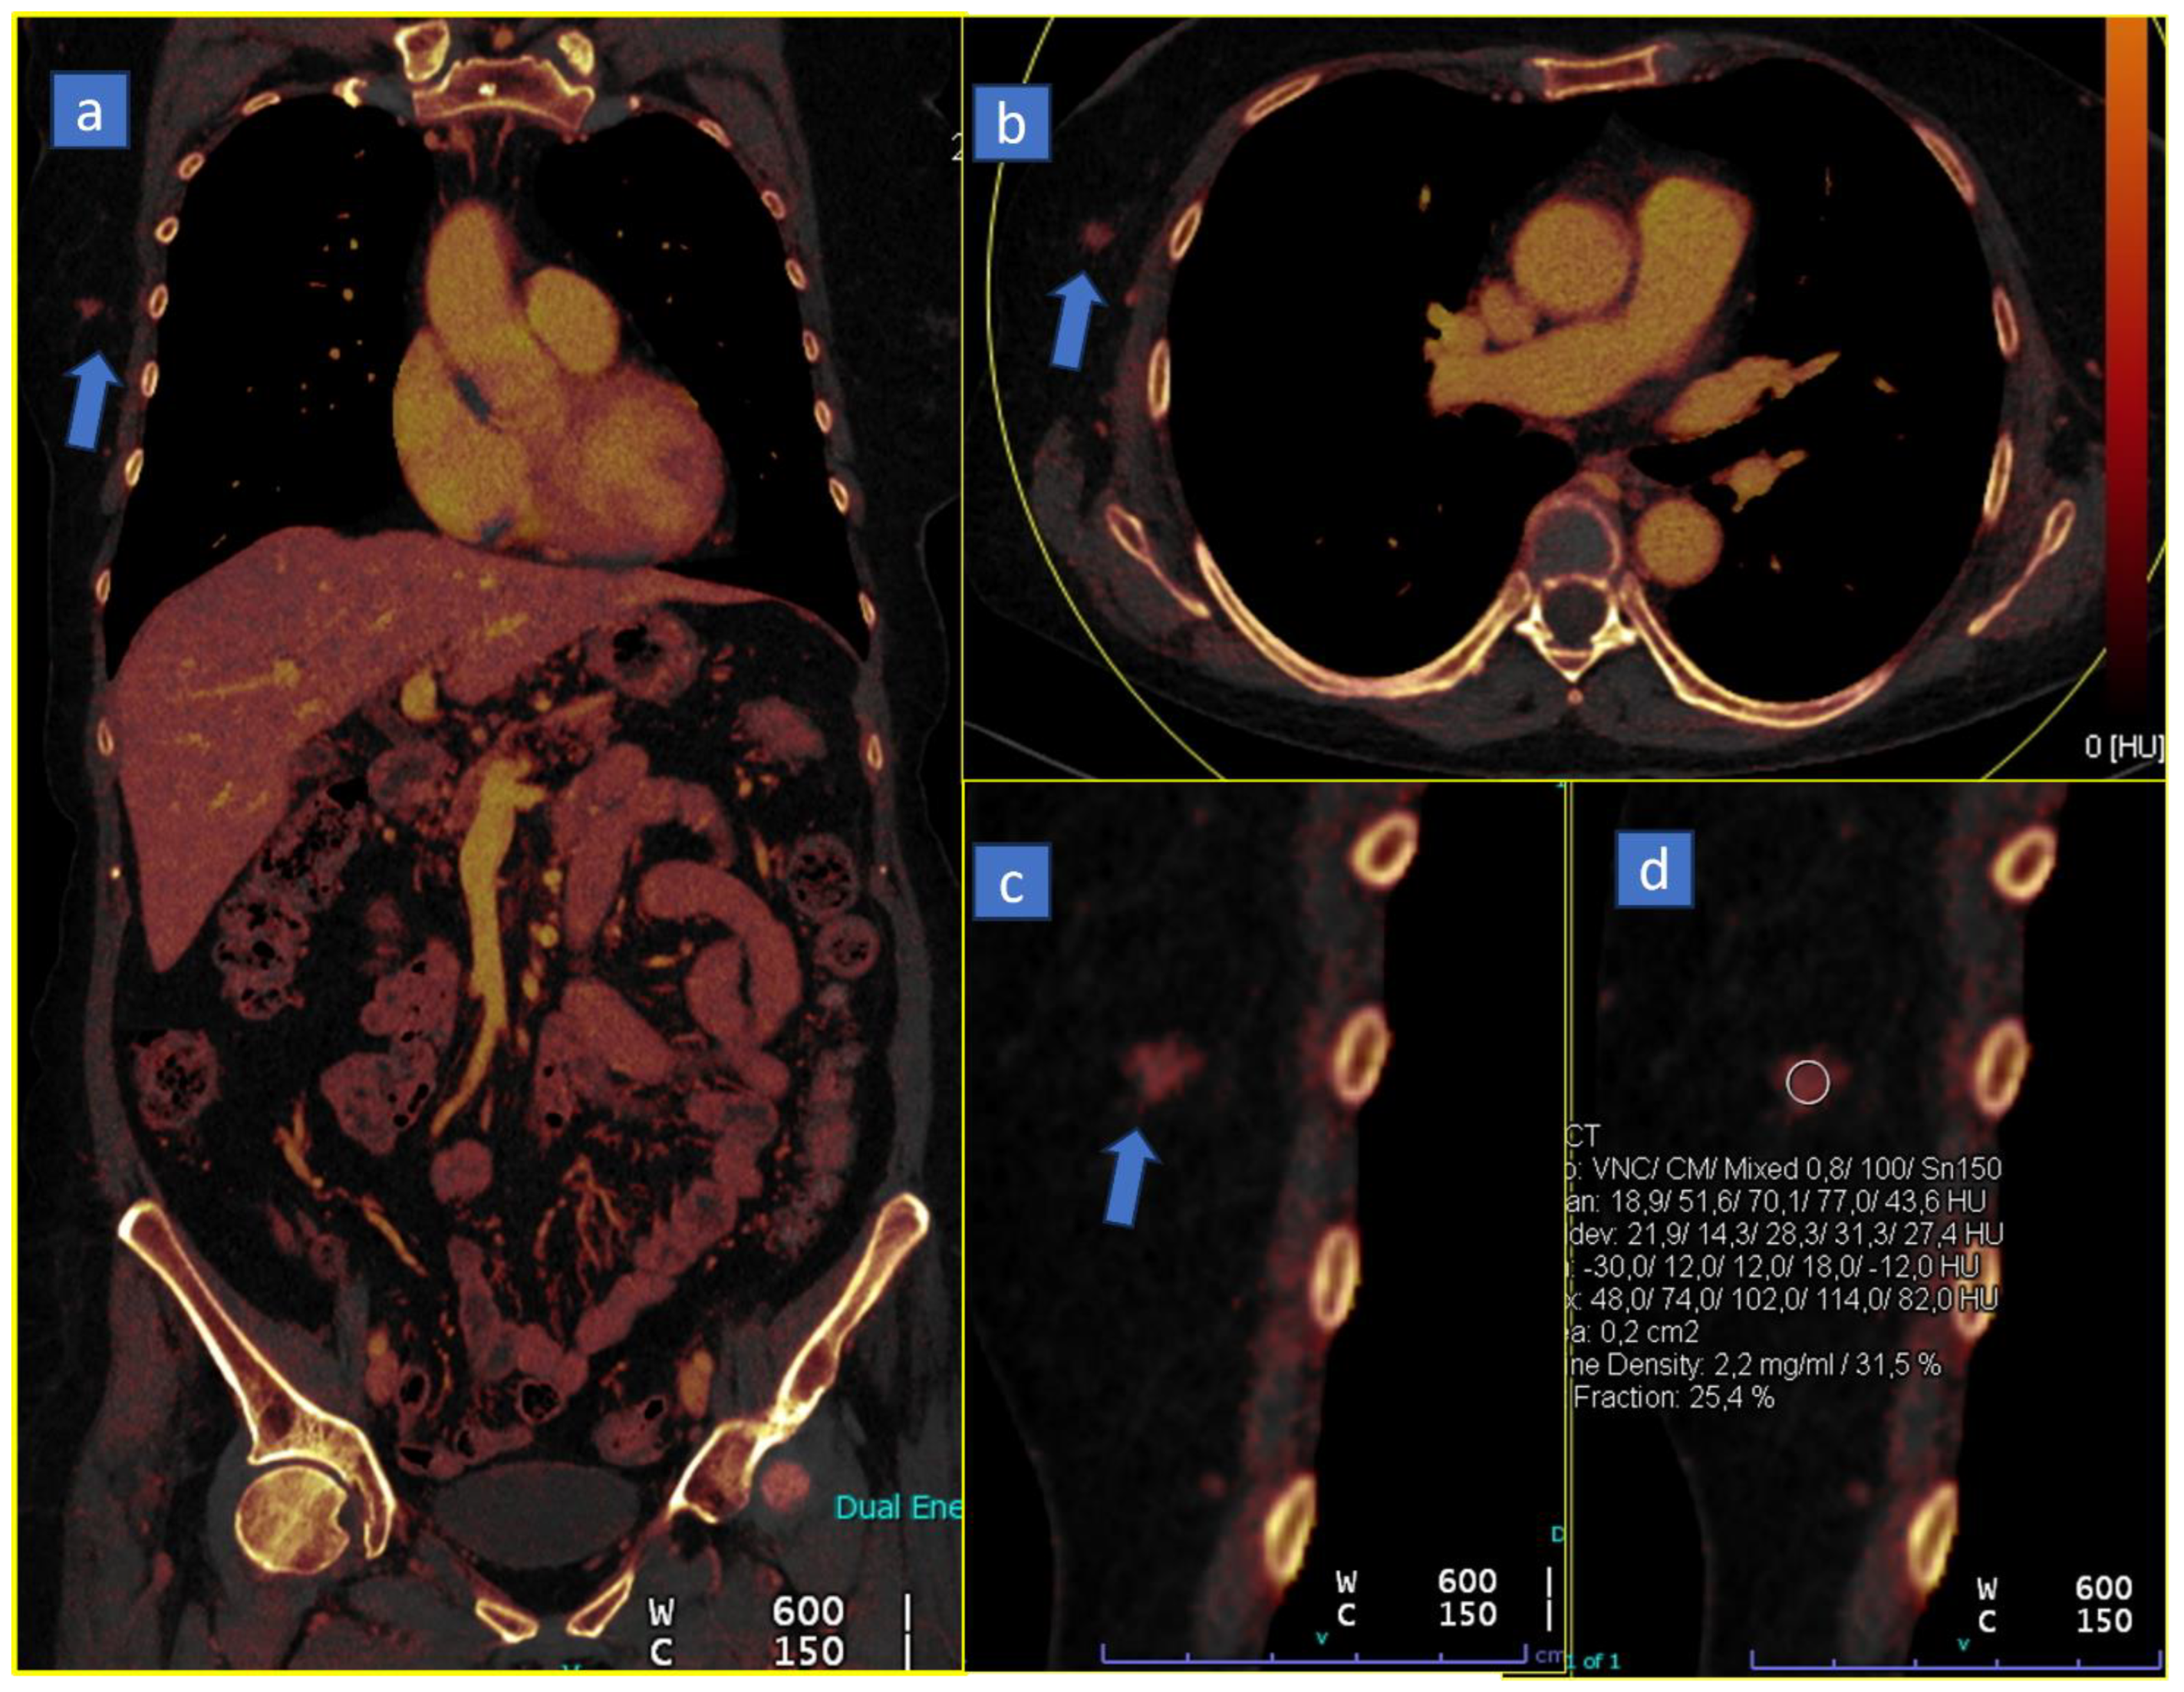

5. Bone Marrow Edema

6. Lung Analysis

6.1. Pulmonary Thromboembolism

6.2. Lung Volumes and Perfusion